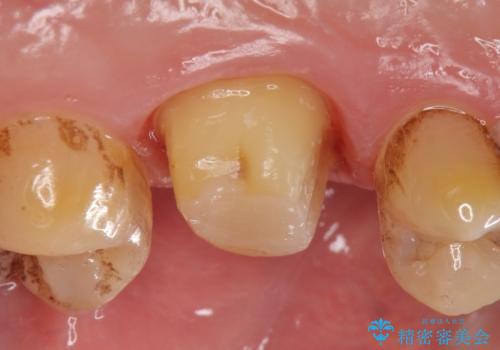

診査の結果左上6は失活していたため、根管治療を行った後にオールセラミッククラウンによる補綴を行いました。

- オールセラミッククラウン…¥100,000、仮歯…¥10,000、ファイバーコア…¥20,000、精密根管治療費別途費用は治療当時の料金となります